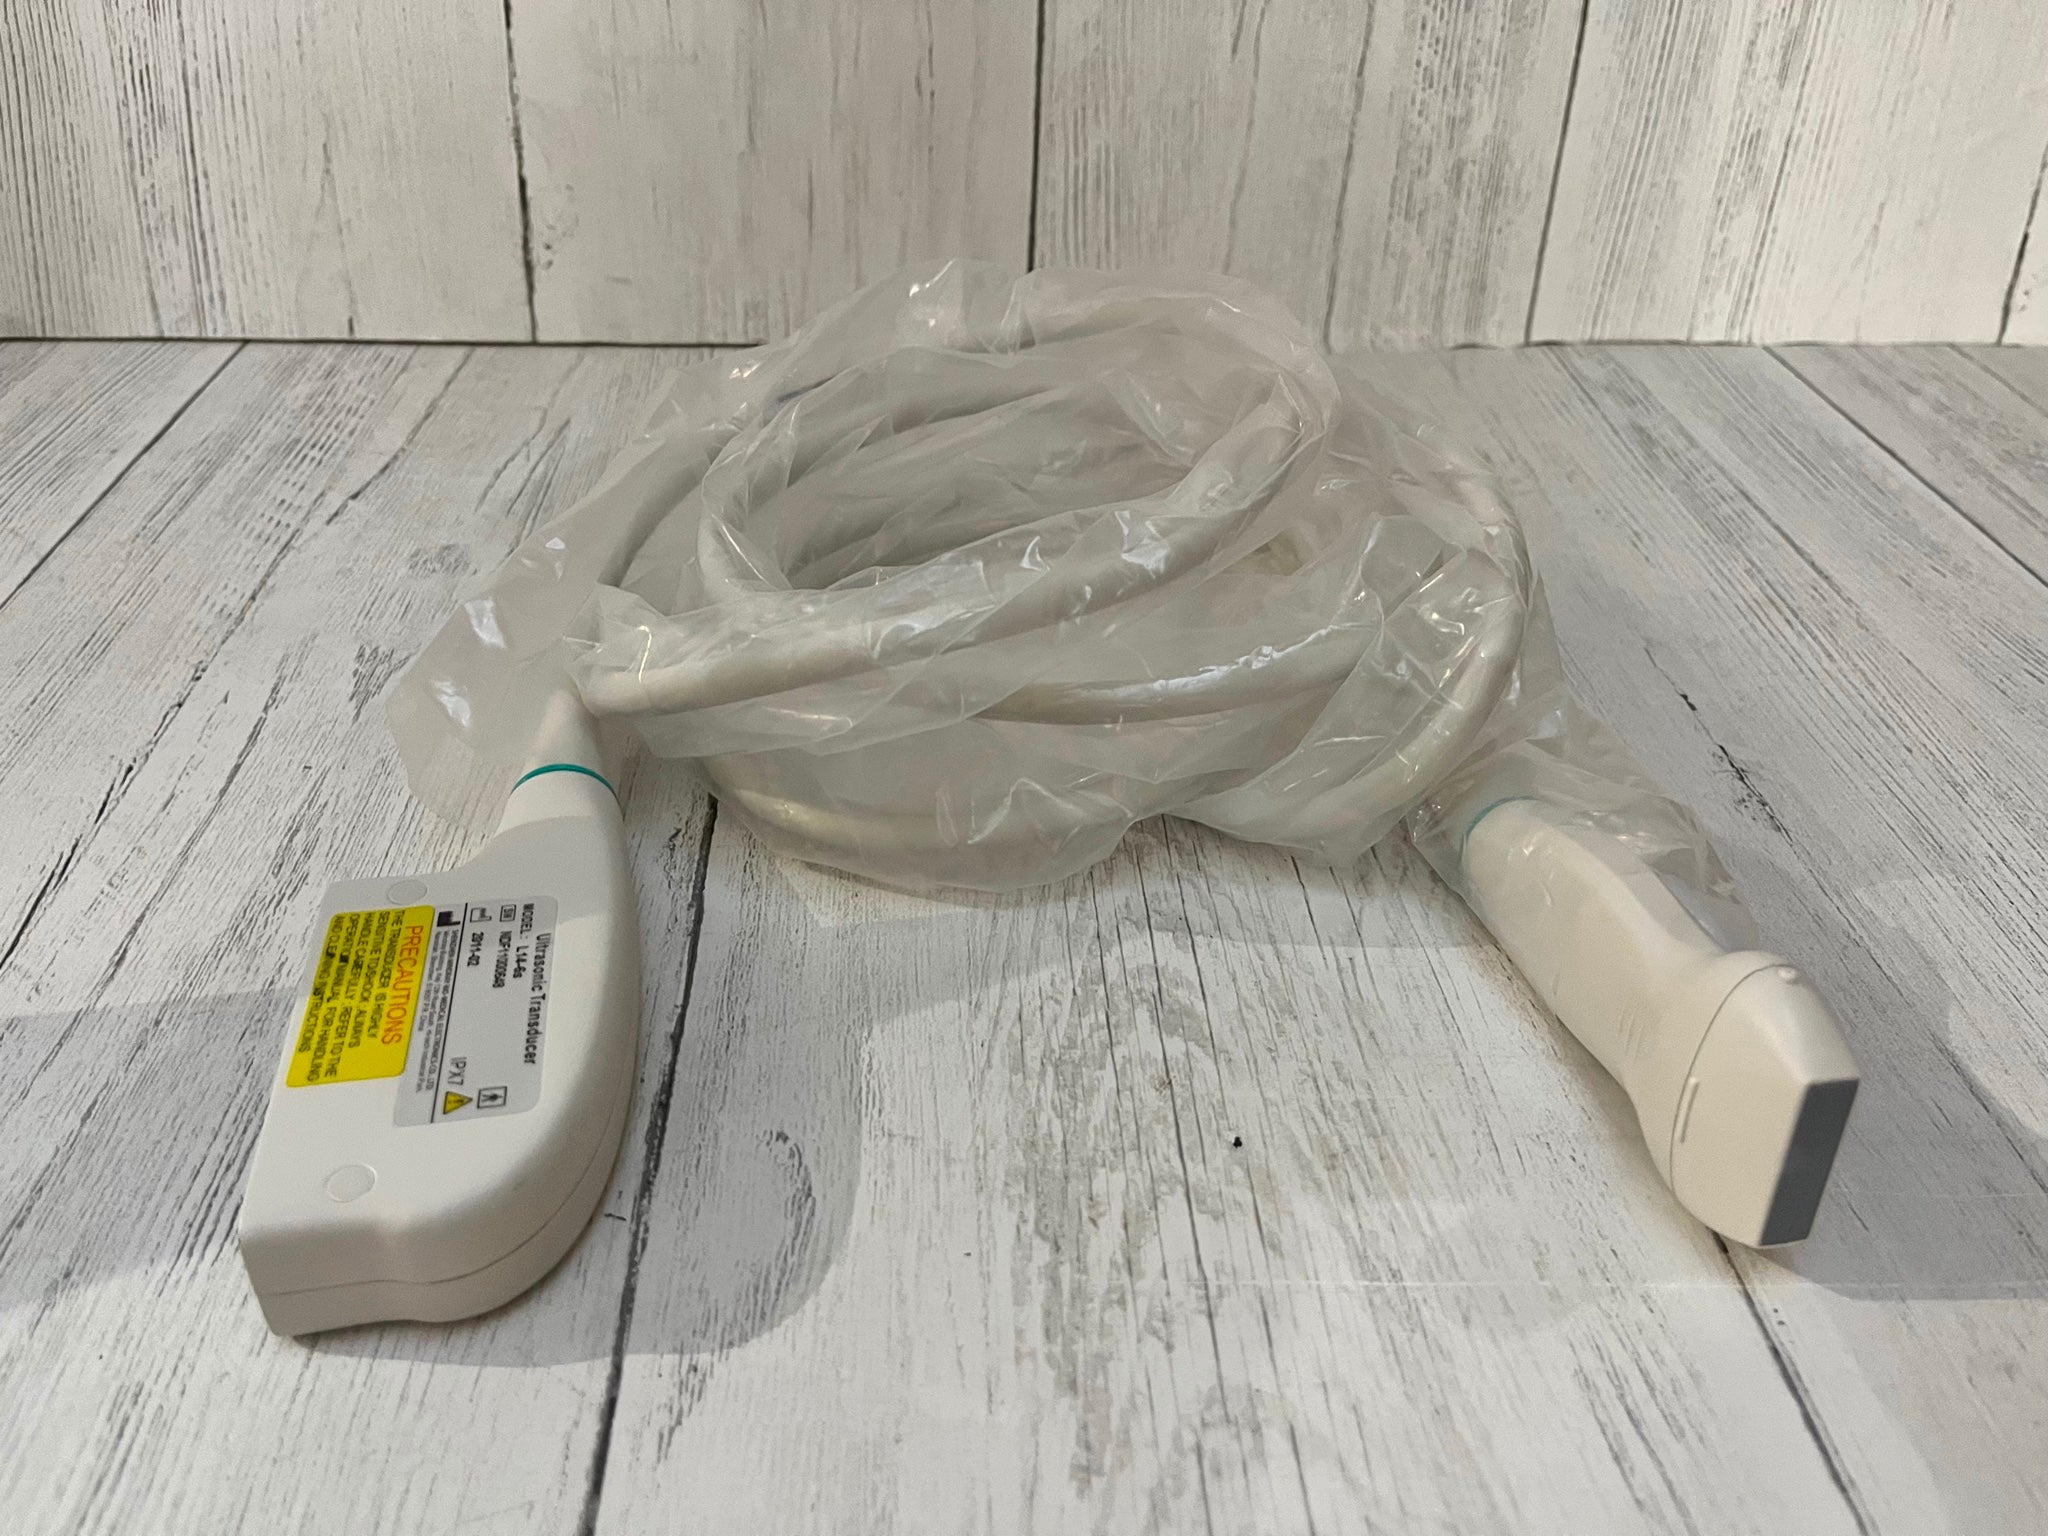

Probe: Convex + Linear + Micro convex heart 3 probes

The Laptop Ultrasound Scanner is an essential tool for healthcare professionals, as it combines Convex, Linear, and Micro Convex probes into one device. This versatility allows for a broad range of imaging applications, making it suitable for various medical settings. Whether you need to visualize abdominal organs or perform superficial assessments, this scanner meets and exceeds expectations. Because of its multiple probe options, medical practitioners can efficiently switch between different imaging modalities without the need for multiple devices.